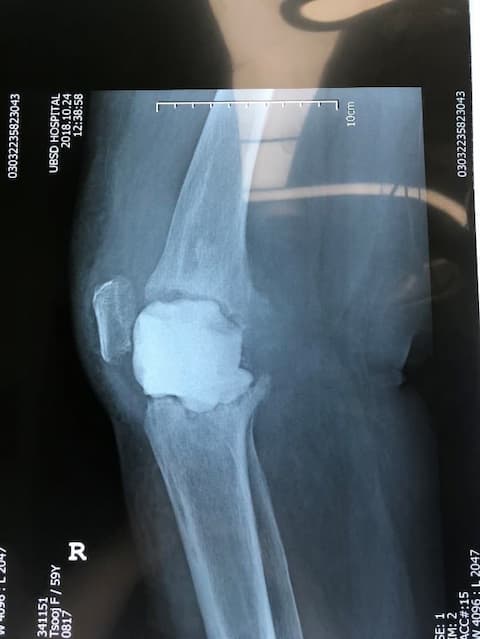

Үе дайрсан ясны анхдагч хавдар, ясны дутмагшлын үед хийгдэх мэс засалimg37Үе дайрсан ясны анхдагч хавдар, ясны дутмагшлын үед хийгдэх мэс засалimg38

Зураг 1. Сэргээн засах мэс заслын өмнөх рентген зураг. Эгц урд, хажуугаас авсан байдал.